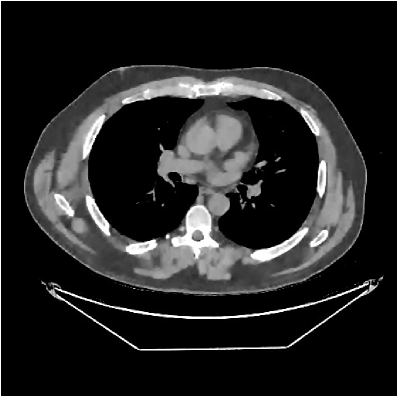

This section compares the reconstruction quality and runtime among the proposed MBIR method, PWLS-ST-, and other three MBIR methods, PWLS-EP, PWLS-DL, and PWLS-ST-. Table I shows that, for both 2D and 3D sparse-view CT reconstructions of the XCAT phantom, the proposed PWLS-ST- model outperforms PWLS-EP and PWLS-ST- in terms of RMSE. In addition, PWLS-ST- using a square transform (of size ) achieves lower RMSE than PWLS-DL using an overcomplete dictionary (of size ) for 2D sparse-view reconstructions. Fig. 3(a) and Fig. 4 show the reconstructed images for 2D and 3D phantom experiments, with different reconstruction models and different number of views. (See the corresponding error maps in the supplement.) The proposed PWLS-ST- consistently gives more accurate image reconstructions compared to other MBIR methods. Specifically, PWLS-ST- has smaller errors in the heart region (see zoom-ins in Fig. 3(a)) of 2D reconstructions than PWLS-DL and PWLS-ST-. In addition, compared to PWLS-ST-, PWLS-DL and PWLS-ST- have some ringing artifacts around the edges with high transition, e.g., edges between air and soft tissues. (See a comparison of profiles of PWLS-ST- and PWLS-ST- in the supplement.) In particular, PWLS-ST- and PWLS-DL give more visible ringing artifacts for 2D reconstruction from fewer views, and PWLS-ST- has these ringing artifacts for 3D reconstructions regardless of the number of views (see zoom-ins in Fig. 4). Table II reports runtimes of different MBIR methods in reconstructing the -views XCAT phantom scan. (FBPConvNet is a non-MBIR method and its runtime for processing a image is approximately one second with a TITAN Xp GPU.) While providing better reconstruction quality, the proposed Algorithm 1 of PWLS-ST- has shorter runtime compared to the algorithms of PWLS-DL and PWLS-ST- in Section III-A. Similar to the PWLS-EP algorithm, the reconstruction time of the PWLS-DL, PWLS-ST-, and PWLS-ST- algorithms can be further reduced by using ordered subsets [51].

Fig. 3(b) shows that when tested on the clinical scan data, the proposed PWLS-ST- method improves reconstruction quality in terms of noise and artifacts removal (e.g., see zoom-ins for soft-issue regions), and edge preservation (e.g., see zoom-ins for bone regions), compared to PWLS-EP and PWLS-ST-. Compared to PWLS-DL, PWLS-ST- achieves comparable image quality, but requires less computational complexity.

The benefit of the proposed PWLS-ST- over PWLS-ST- can be explained when there exist some outliers for some : in (12) gives equal emphasis to all sparse codes – from small to large coefficients that generally correspond to edges in low- and high-contrast regions, respectively – in estimating ; however, PWLS-ST- adjusts to mainly minimize the outliers, i.e., it may not pay enough attention to reconstruct regions with small coefficients. The histogram results in Fig. 1 reveal model mismatch of PWLS-ST- over the iterations. Fig. 3, Fig. 4, and Table I show that PWLS-ST- can moderate model mismatch, and provides more accurate reconstruction than PWLS-ST-.

III-B3 Generalization Capability Comparisons between a “Denoising” Deep NN and the Proposed PWLS-ST- Method

This section compares the generalization capabilities between the proposed MBIR method, PWLS-ST-, and a denoising deep NN, FBPConvNet [14], that are trained from the phantom data; in particular, we tested the trained PWLS-ST- and FBPConvNet models to phantom and clinical scan data. The results in Fig. 6 show that the non-MBIR FBPConvNet method has higher overfitting risks, compared to the proposed PWLS-ST- MBIR method. When tested on clinical scan data, PWLS-ST- achieves much more accurate reconstruction, compared to FBPConvNet. See Fig. 6(b). When tested on phantom data, FBPConvNet generates more unnatural features as the number of views reduces, although it gives lower RMSE values compared to PWLS-ST-. See zoom-ins in Fig. 6(a). The FBPConvNet results above correspond to those in the recent work [16] that FBPConvNet [14] generated some unexpected structures.